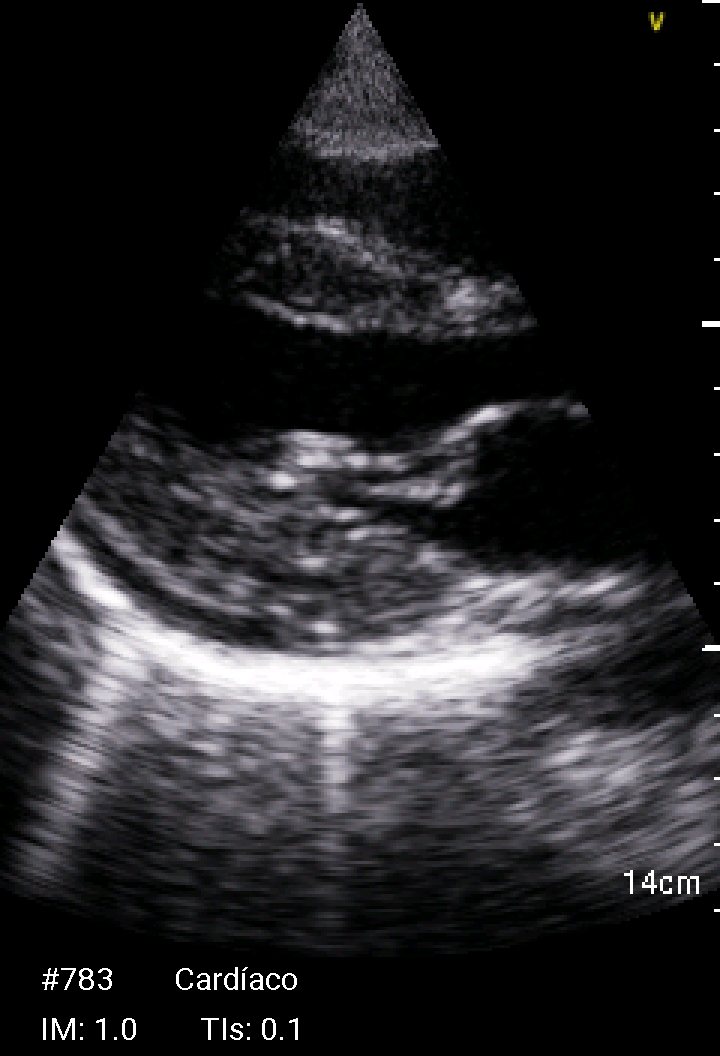

Ante la presencia de fiebre y soplo cardiaco se realiza ecocardioscopia.

Ecocardioscopia: Válvula mitral con engrosamiento de ambas valvas e imagen nodular no móvil en cara auricular del velo anterior (cambios degenerativos versus vegetación). Ventrículo izquierdo no dilatado ni hipertrófico, FEVI preservada. Ventrículo derecho normal. Mínimo despegamiento de hojas pericárdicas en cara posterior.